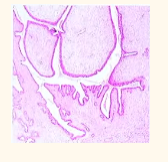

A 40-year-old female with a lump in the breast measuring 5 X 6 cm. The HPE (Histopathological Examination) given in the image, what is the likely diagnosis?